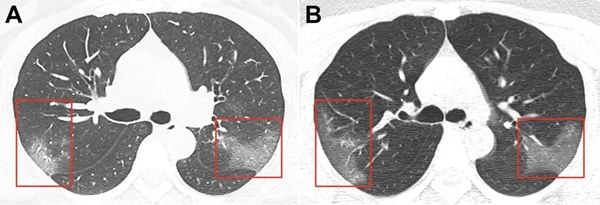

Vài bệnh nhân thở hổn hển khi họ chỉ đi bộ, theo South China Morning Post. Ảnh chụp cắt lớp phổ của 9 bệnh nhân cho thấy dấu hiệu tổn thương.

Ảnh chụp CT phổi của bệnh nhân Covid-19. Các mảng trắng mờ cho thấy phổi đầy dịch. Ảnh: Business Insider.